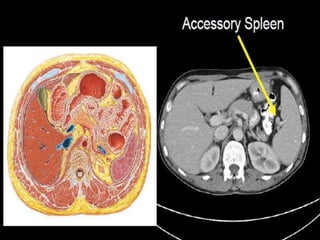

CT cross sectional anatomy.

MRI anatomy images of the abdomen.